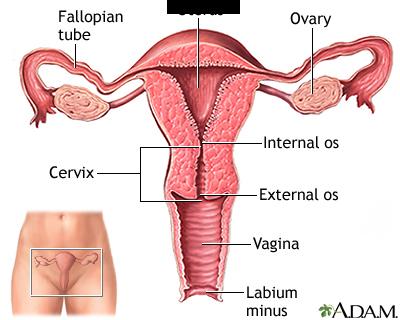

Uterine (=fallopian) tube

Ovary

Uterus

Cervix

Vagina

Endometrium

Myometrium

Perimetrium

Fimbriae

Mature (=Graafian, = antral) follicle

Primordial/primary/secondary follicle

Overian ligament

Round ligament (of uterus)

Broad ligament

Labia majora/minora

Vaginal orifice

Clitoris